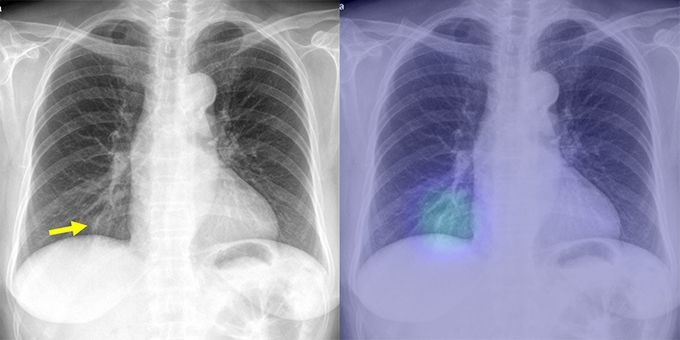

[µ¥Àϸ®¸Þµð ¹Ú´ëÁø ±âÀÚ] ¹Úâ¹Î ¼­¿ï´ëº´¿ø ¿µ»óÀÇÇаú ±³¼ö´Â ÁÖ¿ä ÈäºÎ 4´ëÁúȯ ¸ðµÎ¸¦ ãÀ» ¼ö ÀÖ´Â ÀΰøÁö´É º¸Á¶Áø´Ü ½Ã½ºÅÛÀÌ ¿Ï¼ºµÆ´Ù°í 1ÀÏ ¹àÇû´Ù.

ÈäºÎ 4´ë Áúȯ¿¡´Â Æó¾Ï, Æó°áÇÙ, Æó·Å, ±âÈäÀÌ Æ÷ÇԵȴÙ. ¼¼°èÀûÀ¸·Î ¹ßº´ ºóµµ¿Í »ç¸Á·üÀÌ ³ô¾Æ Á¤È®ÇÑ Áø´ÜÀ» ÅëÇÑ Á¶±â Ä¡·á°¡ ¸Å¿ì Áß¿äÇÏ´Ù.

¹Ú ±³¼öÆÀÀº À̹ø ÀΰøÁö´É ½Ã½ºÅÛ °³¹ßÀ» À§ÇØ 4´ë ÈäºÎÁúȯ X¼± ¿µ»óÀÚ·á°¡ Æ÷ÇÔ µÈ ÃÑ 9¸¸8,621°ÇÀÇ ÈäºÎ X¼± ¿µ»óÀÚ·á °á°ú¸¦ ÀÌ¿ëÇß´Ù.

¼­¿ï´ëº´¿ø, º¸¶ó¸Åº´¿ø, °­µ¿°æÈñ´ëº´¿ø, À»Áö´ëº´¿ø, ÇÁ¶û½º ±×¸£³ëºí ´ëÇк´¿ø¿¡¼­ ¼º´ÉÀ» °ËÁõÇßÀ¸¸ç, ¿ÜºÎ±â°ü Æò°¡ Áø´Ü Á¤È®µµ°¡ Æò±Õ 97% ÀÌ»óÀ¸·Î ¸Å¿ì ¿ì¼öÇÑ °á°ú¸¦ º¸¿´´Ù.

¿µ»óÀÇÇаú Àü¹®ÀǸ¦ Æ÷ÇÔÇÑ 15¸íÀÇ ÀÇ»ç¿ÍÀÇ ºñ±³Æò°¡¿¡¼­µµ ÀΰøÁö´ÉÀÌ ´ëºÎºÐÀÇ ÆÇµ¶Àǻ纸´Ù ³ôÀº Áø´Ü Á¤È®µµ¸¦ º¸¿´´Ù. ÀÇ·áÁøÀÌ ÀΰøÁö´É º¸Á¶¸¦ ¹ÞÀ» °æ¿ì ÃÖ´ë 9%±îÁö ÆÇµ¶´É·ÂÀÌ Çâ»óµÆ´Ù.

°³¹ßµÈ ÀΰøÁö´É ½Ã½ºÅÛÀº ȯÀÚÀÇ ÈäºÎ X¼± ¿µ»óÀ» ºÐ¼®ÇØ ÀÌ»ó ¼Ò°ßÀÌ ÀÖ´Â ºÎÀ§¸¦ Ç¥½ÃÇÏ°í ±× °¡´É¼ºÀ» È®·ü °ªÀ¸·Î Á¦½ÃÇØ ÁØ´Ù. ÀÇ·áÁøÀº ÀΰøÁö´É ¼ÒÇÁÆ®¿þ¾î µµ¿òÀ¸·Î º¸´Ù ¼Õ½±°Ô ¿µ»óÁø´ÜÀ» ³»¸± ¼ö ÀÖ°Ô µÈ´Ù.

¹Úâ¹Î ±³¼ö´Â À̹ø¿¡ º¸¿ÏµÈ ½Ã½ºÅÛÀº ¹ßº´ ºóµµ¿Í Á߿䵵°¡ ³ôÀº ÈäºÎÁúȯÀ» ÇÑ ¹ø¿¡ È®ÀÎ ÇÒ ¼ö ÀÖ¾î ÀÓ»ó¿¡ º¸´Ù È¿°úÀûÀ¸·Î Ȱ¿ëÇÒ ¼ö ÀÖÀ» °ÍÀ̶ó°í ¸»Çß´Ù.